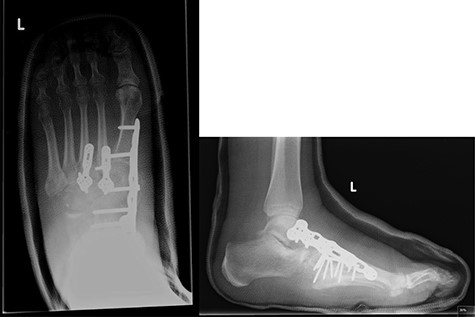

At this presentation, plain film X-ray revealed complete fracture dislocations of the second to fifth tarsometatarsal joints, involving the lateral, middle and medial cuneiform bones of the left mid-foot (Lisfranc fracture dislocations; Fig. 3). This was correlated with bone CT (computed tomography) and MR (magnetic resonance) imaging, with interval changes noted to be of rapid onset (Fig. 4).

Post-operative X-rays (AP and lateral), demonstrating good reduction and fixation of fracture dislocations.

The patient was initially managed with a total contact leg cast, followed by open reduction and internal fixation (ORIF) with locking plates, combined with lengthening of the tendo-Achilles to permit full dorsiflexion and subsequent re-casting (Fig. 5). Her post-operative progress was satisfactory, and she is currently non-weight bearing for 6 months post-ORIF.